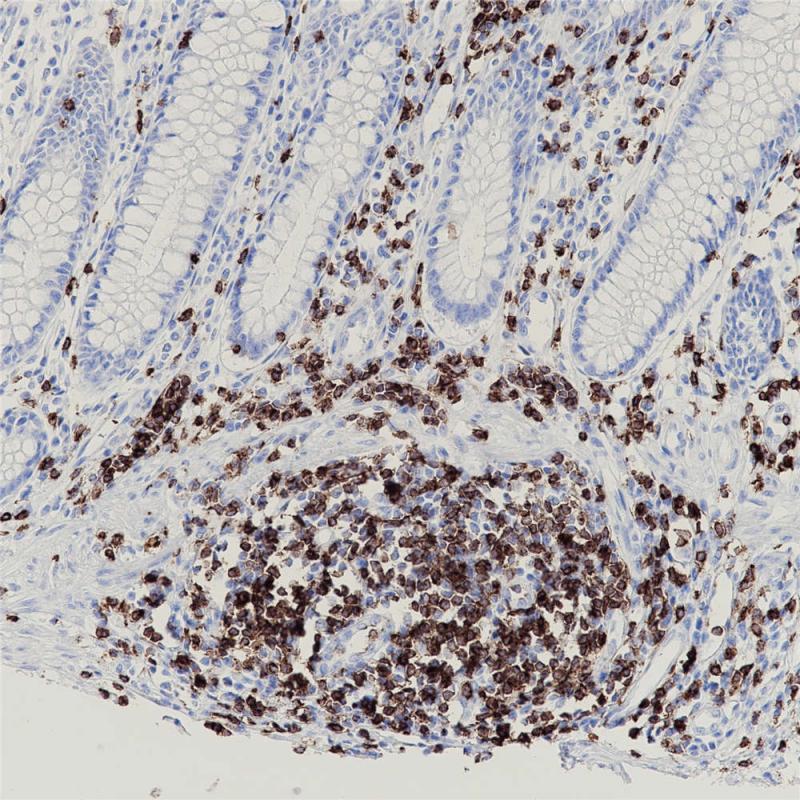

CD2主要存在于成熟的T细胞和NK细胞膜表面, 而B细胞通常不表达,可标记正常T细胞及其相关肿瘤,如前T细胞淋巴瘤、边缘T细胞淋巴瘤和间变大细胞淋巴瘤的诊断与研究。

阳性对照

T细胞淋巴瘤

亚细胞定位